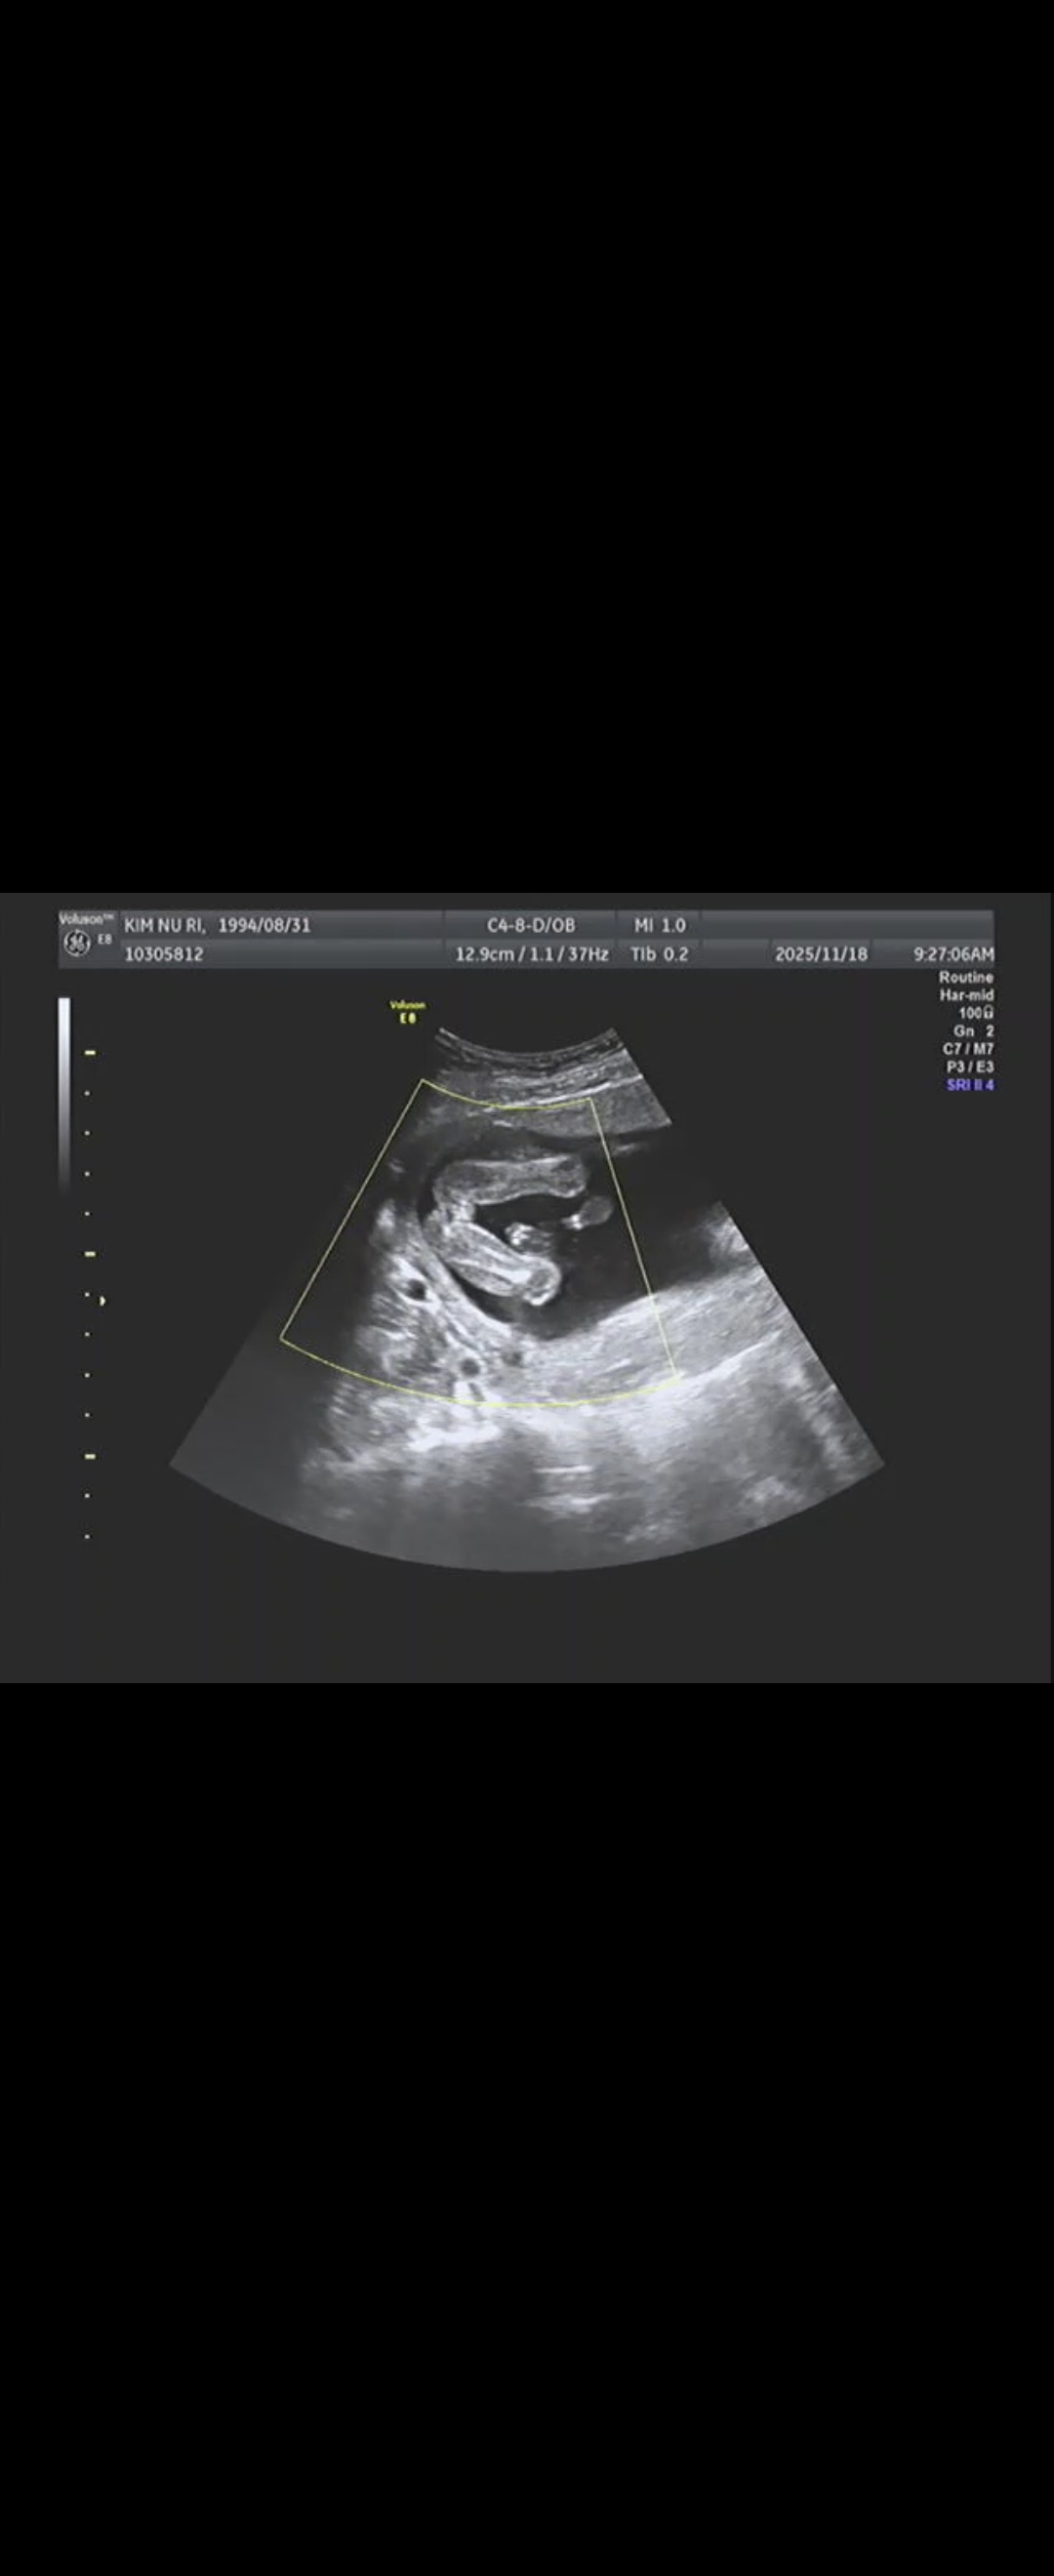

16주 성별확정 초음파사진 공유합니다!

오늘 16주 3일이라 2차기형아 검사하고 성별 확인했습니다! 결과는 딸이었어요 ㅎㅎ 저번 14주때 다리사이 초음파 투표 올렸을때 거의 다 아들이라고 투표를 해쥬셔서 아들인가보다...하고있었는데 그것은 탯줄이었나봐요! 의사선생님이 보자마자 바로 딸이라고 확실하게 말씀해주시더라구요. 다리사이 초음파 비교 필요하신 분들을 위해 사진 공유해봅니다 ㅎㅎ 다같이 건강히 무사히 만출합시다❤️